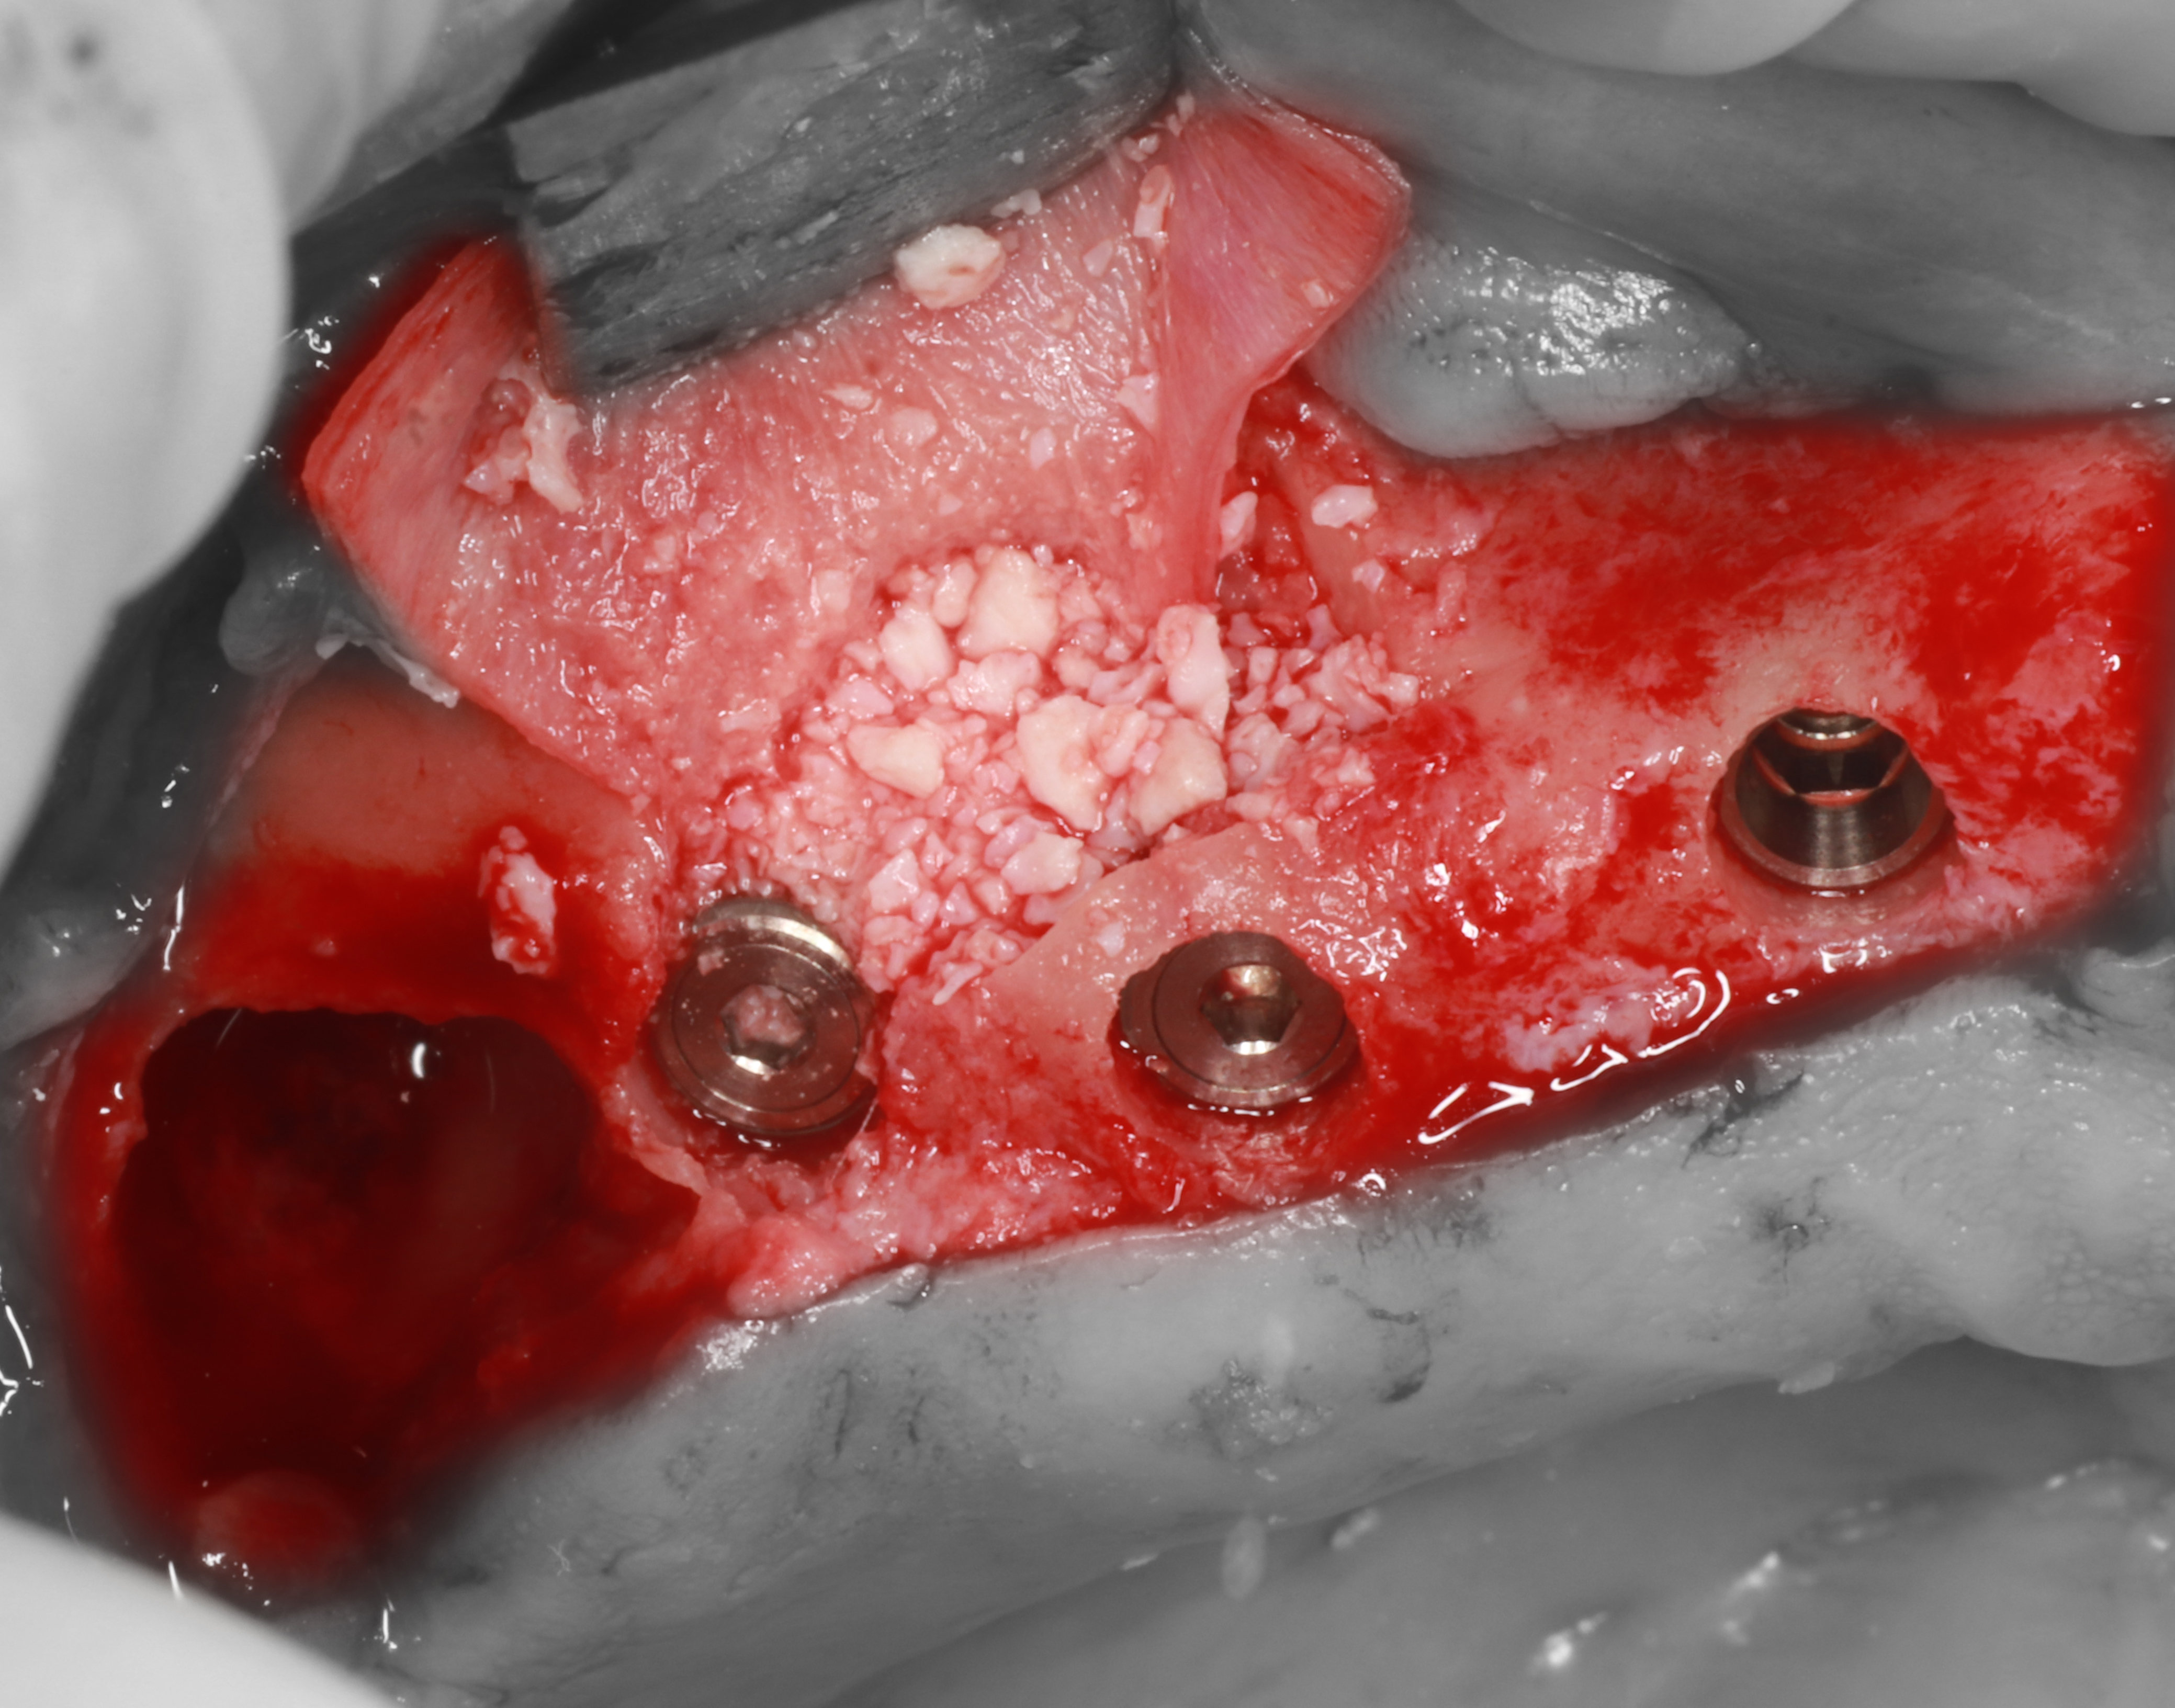

6) Перфорации изолированы с помощью коллагеновой мембраны, установлены имплантаты ICX.

7) Проведена аугментация субантрального пространства с помощью ксеногенного костнозамещающего материала BioOss.